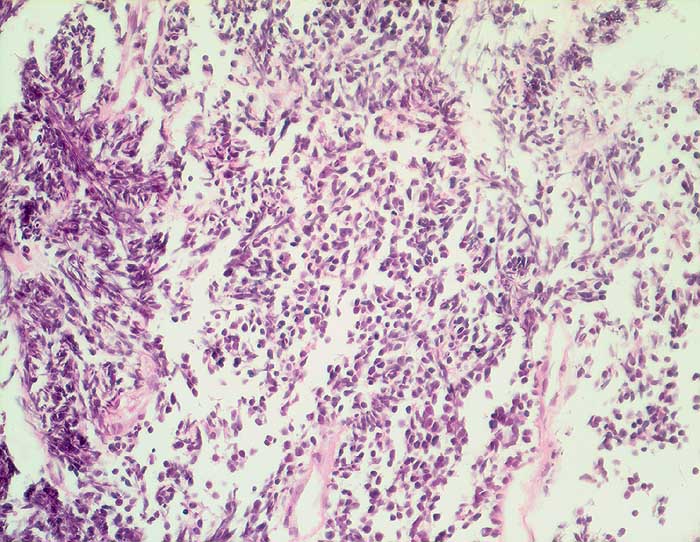

Kleinzelliges Karzinom

Rasen kleiner nacktkerniger Tumorzellen mit ausgeprägten Quetschartefakten aufgrund fragiler Kerne.

Tumor im Lungenmittellappen

Histologie

400